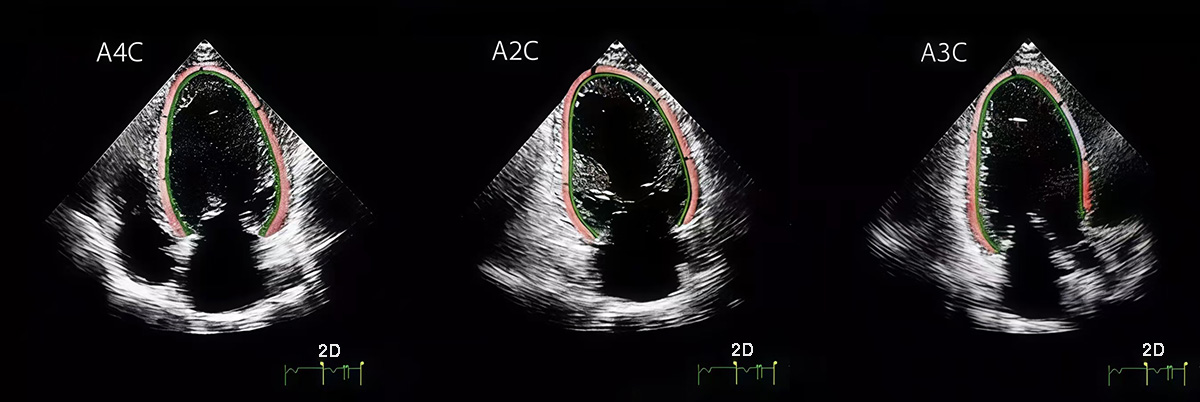

LVGLS was assessed using a Philips EPIQ7 ultrasound system (manufacturer: Philips Healthcare, Amsterdam, Netherlands) equipped with a 2.5–5 MHz phased-array transducer. Standard apical 4-chamber (A4C), 2-chamber (A2C), and 3-chamber (A3C) views were obtained at end-expiration, with frame rates maintained between 40–80 frames per second. LVGLS was quantified via speckle-tracking STE using QLab Cardiac Motion Quantification software (v11.0, Philips Ultrasound, Bothell, Washington, USA), by analyzing myocardial deformation across the three apical views. The final LVGLS value was calculated as the arithmetic mean of the strain measurements from A4C, A2C, and A3C views. Manual adjustment of region-of-interest boundaries was performed to ensure complete myocardial wall coverage (Fig. 2).

Fig. 2. LVGLS was obtained by analyzing standard A4C, A2C, and A3C views using Qlab strain analysis and calculated from these three views. LVGLS, LV global longitudinal strain; A4C, apical 4-chamber; A2C, apical 2-chamber; A3C, apical 3-chamber. The red and green lines represent the LVGLS sampling lines along which data were collected.